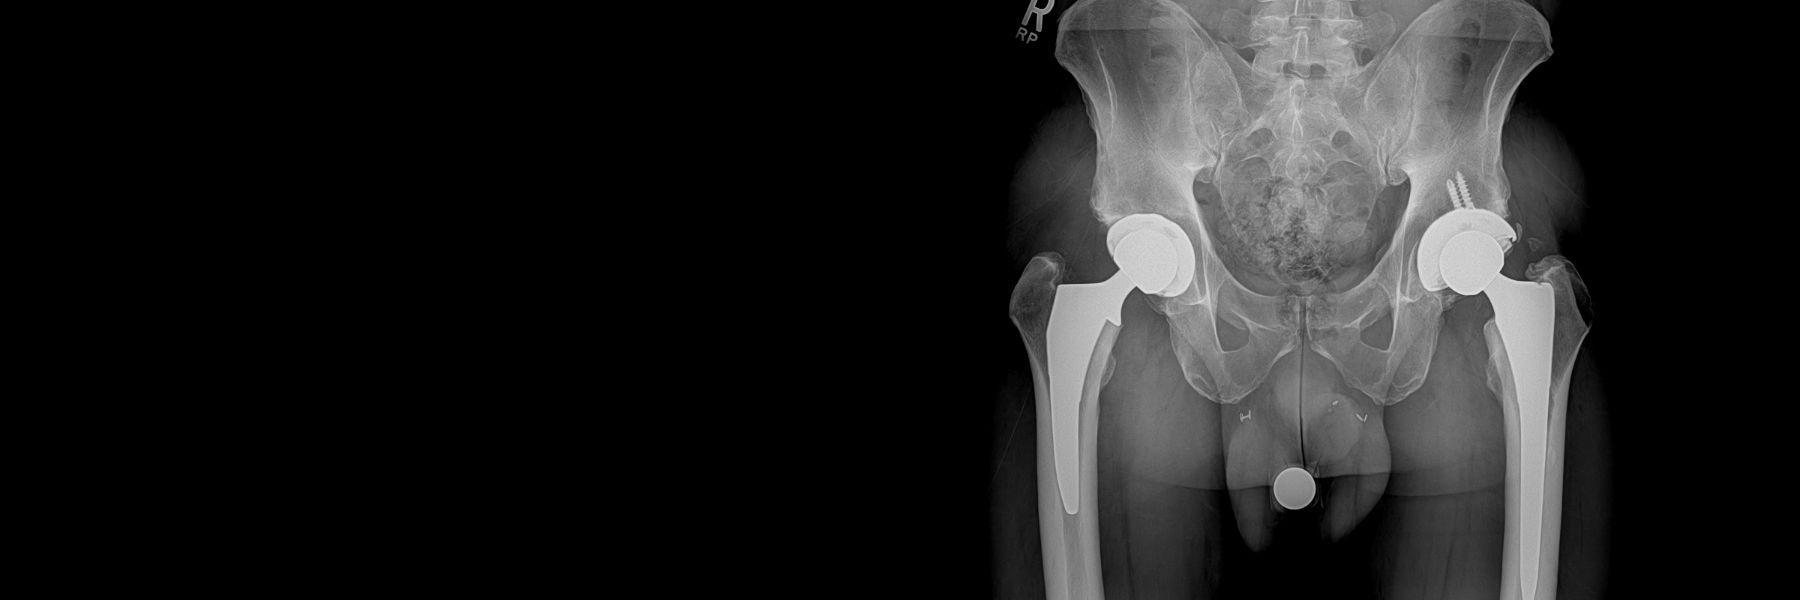

Total hip replacement surgery is a tremendously successful procedure for eliminating pain and restoring function in patients with severe hip arthritis. Most simply put, a total hip replacement involves removal of the damaged cartilage and bone from the ball and socket of the patient’s arthritic hip and replacing these with a new ball-and-socket implant that allows the patient to walk with smooth motion and without pain.

During a hip replacement using the Direct Anterior Approach, the patient is positioned supine on a traction table (the Hana® table) that allows independent positioning of the limbs during surgery. This position facilitates the use of C-arm fluoroscopy. C-arm fluoroscopy is an intra-operative x-ray camera that projects images on a computer monitor in the operating room and is used to navigate the position of the hip socket and stem in real-time during the procedure. The fluoroscopic images are analyzed by computer software (OrthoGrid Systems, Inc.), which registers multiple anatomic landmarks in order to calculate socket position, leg length, and offset. This allows the surgeon to make small adjustments intra-operatively, in order to ensure an anatomic reconstruction.